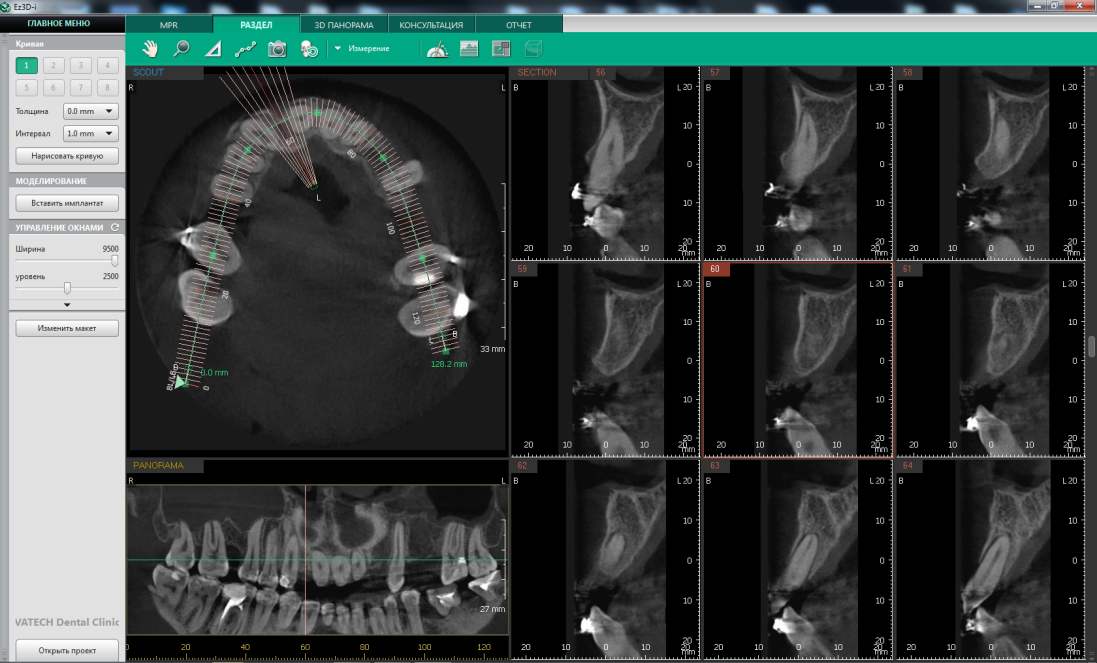

Специализированная программное обеспечение Ez3D-i V4.3.0 от Vatech (Рис.1.) , обрабатывающее данные конусно-лучевой компьютерной томографии, значительно облегчает планирование операции и последующую диагностику. Приложение создает трехмерные реконструкции изображения, представляя максимально полную информацию о степени атрофии костной ткани альвеолярного отростка, что существенно повышает точность проведения операции дентальной имплантации и предимплантационных вмешательств, а также прогнозирования результата хирургического вмешательства.

• - оценка очагов резорбции апикальных и периапикальных тканей (Рис.1).

Рис.1 Программное обеспечение Ez3D-i V4.3.0 от Vatech. Дентальная объемная томограмма. Оценка топографии и анатомии корневых каналов